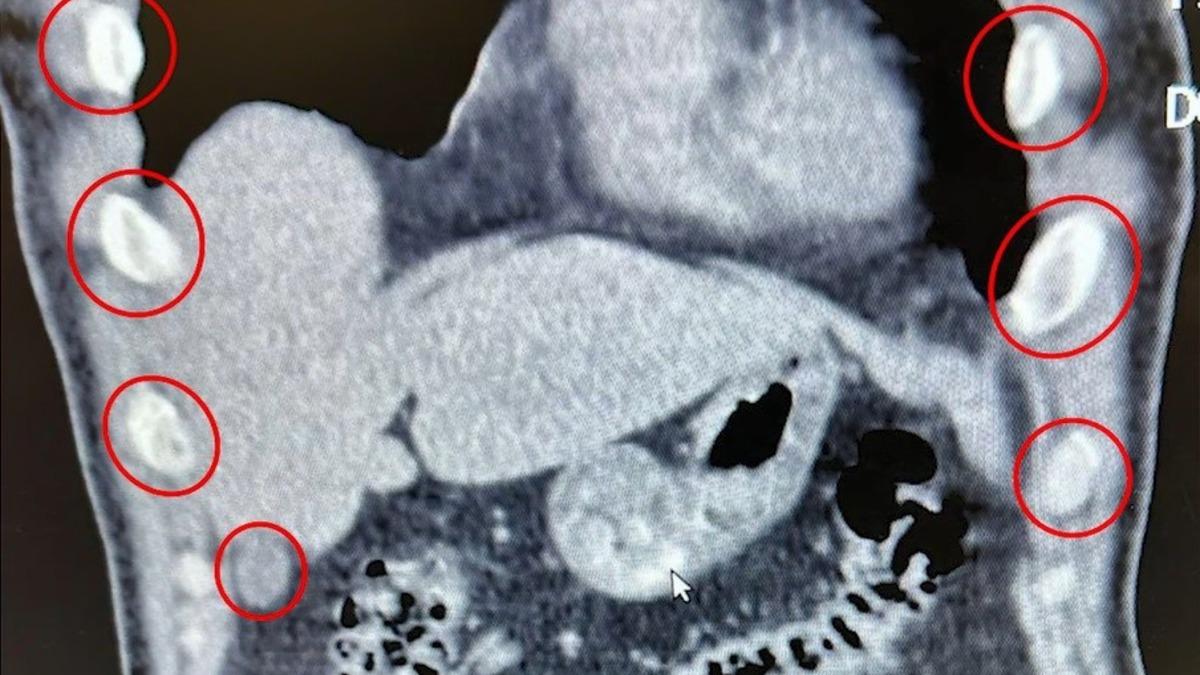

Şahısların yapılan tıbbi müdahalesinde, yuttukları 136 kapsül halinde toplam 1 kilo 48 gram metamfetamin ele geçirildi.